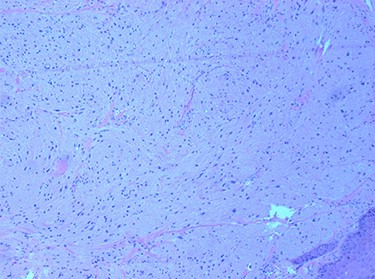

Histopathological examination revealed large cells with granular eosinophilic cytoplasm and nuclei with scattered mild to moderate atypia. These cells expressed CD68, CD56 and S100, and lacked expression of AE1 and AE3. Focal spindling of cells was present with no obvious necrosis or mitosis. The squamous surface epithelium was orthokeratizing with mild pseudoepitheliomatous hyperplasia (Figs 5 and 6).

tumour cells staining positive for S-100 on immunohistochemistry.

Macroscopically, the final specimen demonstrated a white submucosal epiglottic nodule (Fig. 8). Immunohistochemistry showed GCT (strongly positive for S-100 protein and weakly positive for CD68). Microscopically, tumour cells had abundant granular cytoplasm that was periodic acid-Schiff (PAS) positive and diastase resistant; these cells were closely associated with some nerve fibres. The tumour abutted the epiglottic cartilage. The closest margin was <1 mm inferiorly with good clearance (≥3 mm) at other mucosal margins. There was no evidence of necrosis, atypical mitoses or increased mitotic activity.

GCT can be identified by histopathological studies using haematoxylin and eosin (H&E) staining, which shows polygonal, large cells clustered in nests or sheets with coarsely granular eosinophilic cytoplasm [5, 7–9]. Malignant GCTs are characterized by histologic features such as tumour necrosis, increased mitotic index and spindling of cells, but clinical behaviour such as metastasis must also be taken into account [9]. Immunohistochemical staining of GCT has been shown in the literature to be positive for S-100 protein [1, 3–10], PAS [7, 9, 10], neuron-specific enolase [3–7, 9], vimentin [5, 7] and CD68 [6, 7, 9, 10]. In our case, S-100 and CD68 were positive with PAS. The presence of pseudoepitheliomatous hyperplasia (reactive epithelial proliferation with pseudoinfiltrative growth pattern) is common in GCT and can be confounding in some instances, as it may be mistaken for well-differentiated SCC especially if small biopsies are taken [3].